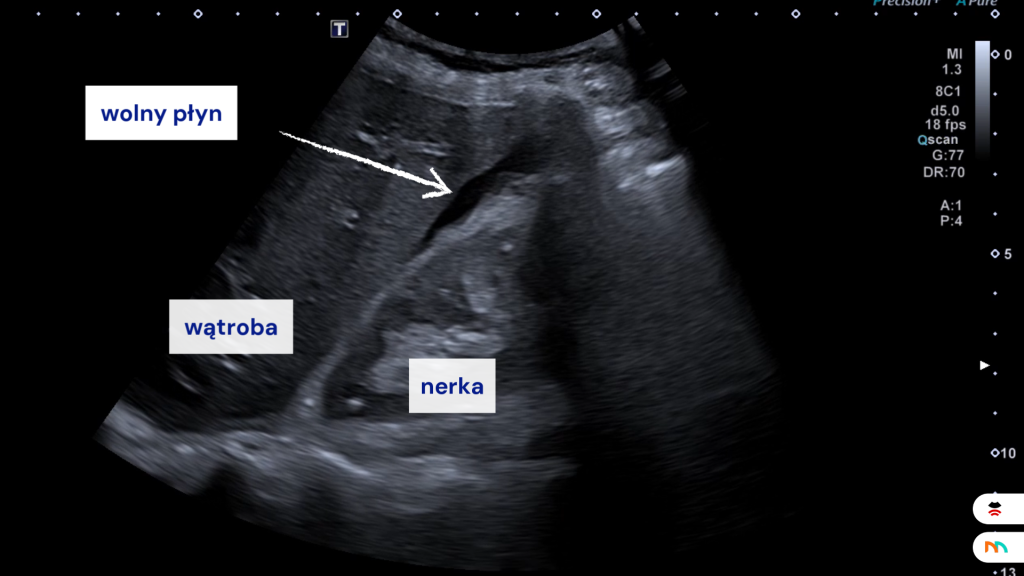

Aby zwiększyć przeżywalność pacjentów dotkniętych urazem oraz dać możliwość prowadzenia diagnostyki obrazowej już w warunkach przedszpitalnych wprowadzono do użytku w 1996 r. protokół USG FAST (Focused Assessment with Sonography for Trauma). Dodatni wynik badania FAST jest jedną z ważnych przesłanek w decyzji o wczesnej interwencji chirurgicznej np. laparotomii. Schemat badania jest bardzo uproszczoną formą pełnego badania ultrasonograficznego jamy brzusznej i jego celem jest odpowiedz na pytanie czy w jamie brzusznej obecny jest wolny płyn.

FAST umożliwia wiarygodną ocenę wolnego płynu w jamie brzusznej poczynając od objętości 200 ml. Protokół ten nie daje bezpośredniej odpowiedzi na pytanie co jest przyczyną krwawienia tylko stwierdza fakt wystąpienia wolnego płynu. Badanie USG wg protokołu FAST wykonuje się w Europie od lat 70-tych. Bardzo szybko znalazło ono wielu zwolenników, w tym wśród lekarzy radiologów, którzy podkreślają pozytywne cechy badania, mogące przyczynić się do zwiększenia szans na przeżycie pacjentów po urazach wielonarządowych.